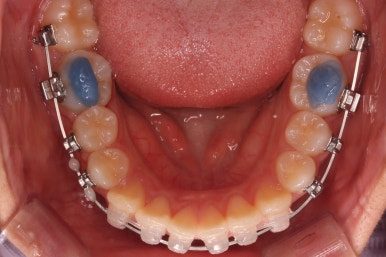

예상한대로 자리만 충분히 마련해주니 그동안 나오지 못하고 막혀있던 치아가 슬그머니 고개를 내밀고 있습니다.

좀 더 기다렸다가 좀 더 올라오면 장치를 부착해서 정리해주기만 하면 되겠습니다.

부산치아교정잘하는곳 키다리아저씨치과에서는 치아가 올라오자마자 장치를 부착하여 가지런하게 해줍니다. 이제 어느 정도 큰 그림은 그려졌다고 보시면 되겠습니다.

어느 정도 큰 그림이 그려졌으면 중앙선이라든지 치아의 디테일한 면을 더 수정하고 마무리하게 되겠습니다.